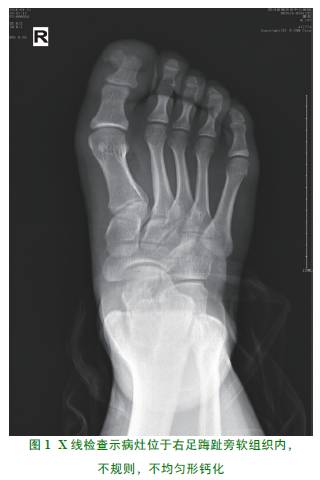

患者,男,15岁,因“发现左踇趾赘生物形成伴增大2月”入院,入院查体:左踇趾远端可见一大小约1*0.8cm,质硬,轻微压痛,表面皮肤无发红,皮温不高,肢体远端感觉及运动正常,走路时无明显跛行。X线片检查见图1:病理大体所见:带少许皮肤的软组织一块,1.3*0.6cm,切面灰白,质硬(详见图2、图3)。

Nora病它代表一种异位的骨化,最常累及手和足骨,长骨受累占25%。典型的X线示有一重度钙化或骨化的肿块,有宽的基底部附着于其下方表现正常的皮质上。